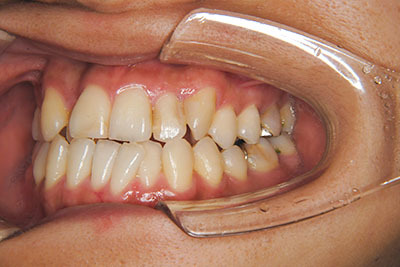

おとなの方でも矯正治療をあきらめないでください!

いくら歯が動き易くとも、本人がやる気でなければ効果は出ませんし、むし歯発生のリスクも高まります。おとなの方は顎の成長が終わっているため、治療の計画が立てやすいとも言えます。「もう大人だから…」とあきらめず、一度ご相談ください。